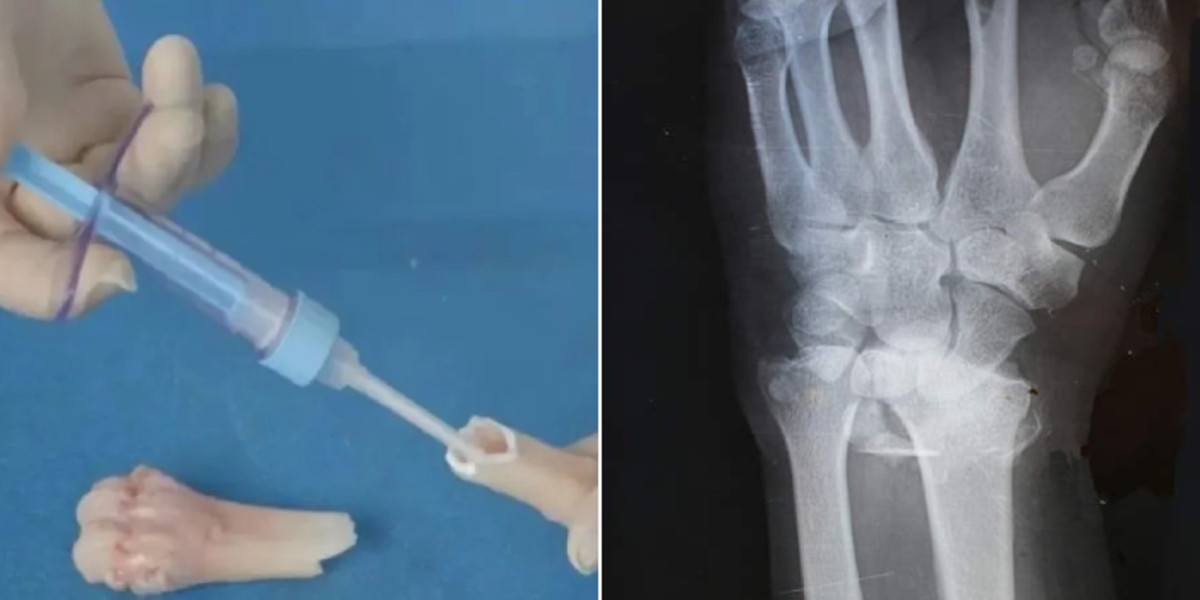

항저우 런런쇼 병원의 정형외과 부주임 린셴펑 박사에 따르면, 이 접착제는 단 한 번의 주사로 "부러진 뼛조각을 3분 만에 붙인다"고 합니다.

린 박사는 혈액이 많은 환경(출혈이 많이 나는 상황 또는 혈관이 밀집된 곳)에서도 2~3분 이내에 정밀한 고정이 가능하다"라고 설명했습니다.

실제 임상 사례에서는 손목 골절 환자에게 3cm 정도의 작은 절개만으로 접착제를 주입한 후 3분 만에 골절 부위가 고정됐습니다.

기존 치료법이었다면 이 환자는 금속판과 나사를 이용한 수술을 받고, 나사를 제거하기 위해 다음 해에 추가 수술을 받아야 하지만, '본-02'를 사용한 후 3개월간의 추적 관찰 결과 환자의 골절은 합병증 없이 완전히 회복된 것으로 나타났습니다.